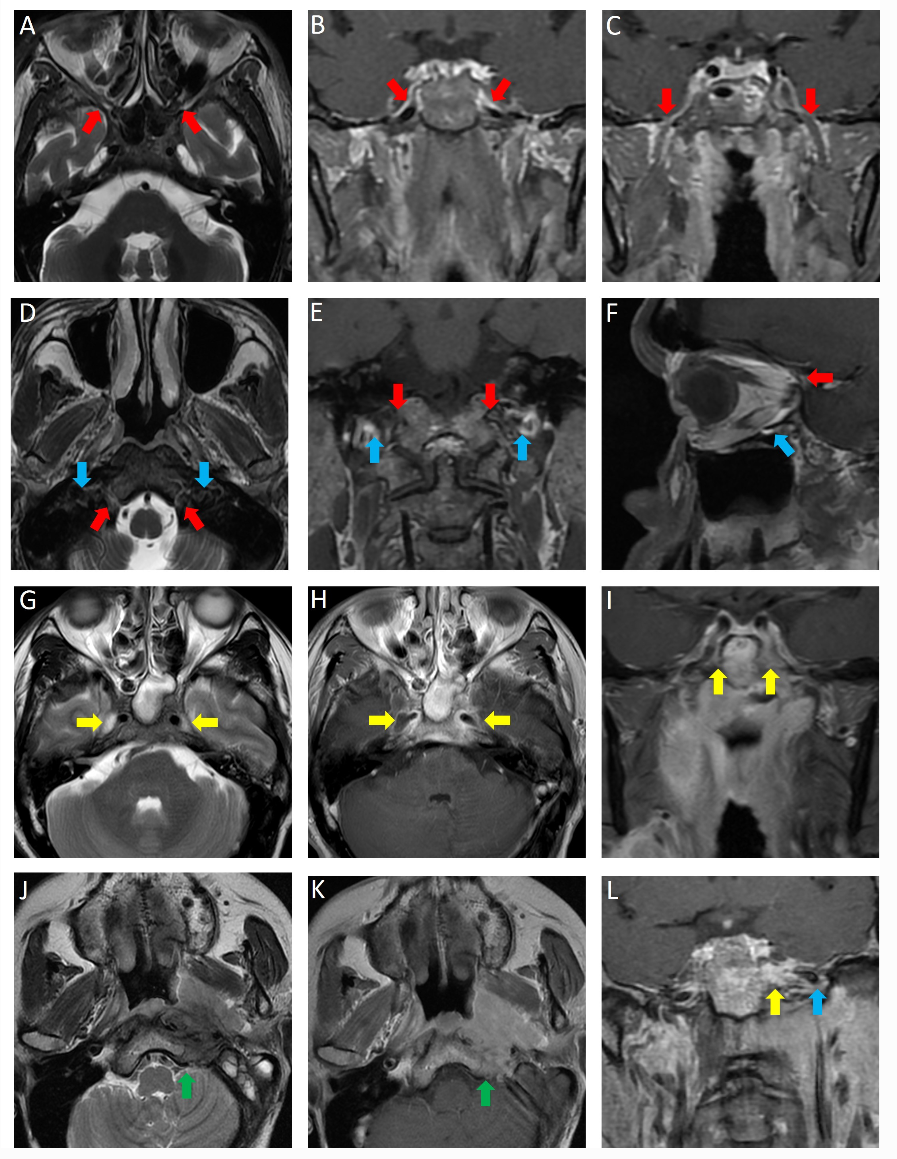

本研究回顾性纳入2010年1月至2014年3月期间就诊于中山大学肿瘤防治中心(1320例)及佛山市第一人民医院(432例)共1752例初诊无转移的鼻咽癌患者。评估的颅底孔道变量包括破裂孔、卵圆孔、翼腭窝、舌下神经管、颈静脉孔、眶上裂及眶下裂;继而运用热图/聚类、网络分析技术,结合患者生存数据,将颅底孔道侵犯根据预后差异分类;通过Kaplan–Meier法绘制生存轨迹、log-rank检验比对差异、多元Cox回归挖掘预后关键,以及1:1随机匹配对剖析诱导化疗疗效。(图1)

图1 各孔道正常解剖位置(A-F)及各孔道侵犯表现(G-L)